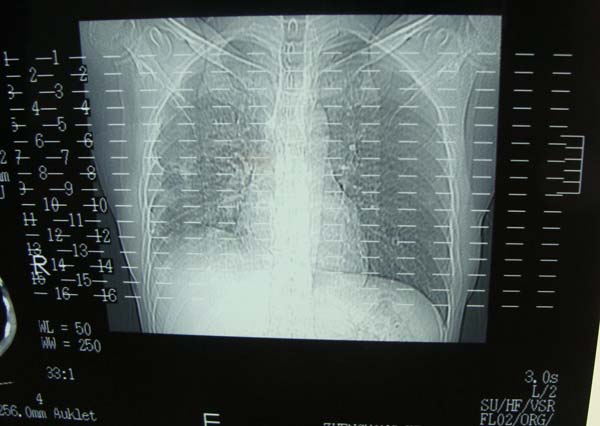

标题: CT15132:男,26岁。建筑混凝土工人。发热。咳。 [打印本页]

标题: CT15132:男,26岁。建筑混凝土工人。发热。咳。

右肺继发型肺结核,右侧胸腔积液、胸膜肥厚粘连。

右肺继发型肺结核,右侧胸腔积液。

年轻男性,右肺多形性病灶伴右侧胸腔积液,考虑结核

右肺继发型肺结核,右侧少量胸腔积液、胸膜肥厚。